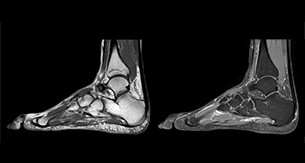

“In peripheral joints, mDIXON TSE imaging aids in diagnosing injuries in ligaments or tendons, for imaging degenerative and inflammatory pathologies such as osteoarthritis and rheumatologic disorders and for oncological exploration.”

“For tendon and ligament assessment around knee, ankle, hip and elbow, mDIXON TSE contributes to diagnostic confidence thanks to having images both with and without fat suppression – and without time penalty. This is possible because 2-point mDIXON is faster than the common 3-point Dixon method. It can also increase efficiency as it helps avoid having to add scans during the exam.”

“mDIXON TSE sequences allow simultaneous characterization of morphological changes from the in-phase T2-weighted images and visualization of edematous changes, thanks to the water T2-weighted images from the same acquisition. Anatomical and morphological considerations could be a partial or complete ligament tear, a bony avulsion or hematoma.”

“For soft tissue assessment mDIXON brings similar benefits. For example in one T2-weighted mDIXON TSE acquisition, having the multiple contrasts helps us assess abnormalities in peripheral nerves fascicles, which may be due to anatomical or inflammatory changes..”